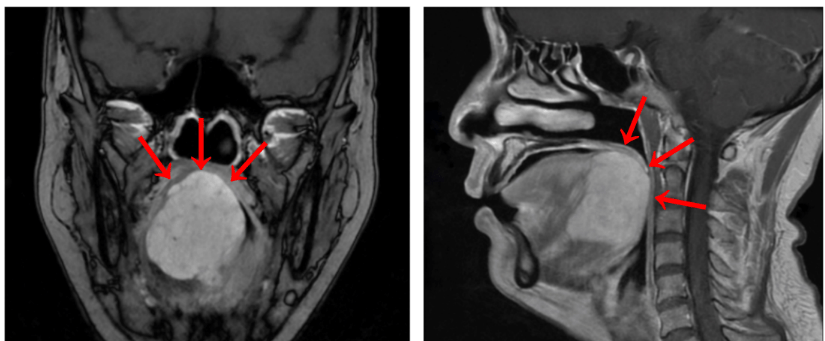

通过专科检查 , 宋明医生发现刘女士的舌根部肿物达到5cm , 几乎占据整个舌根部并向口咽腔突出 。 MRI检查也提示舌根巨大肿块有幼儿拳头大小 , 向前侵犯部分舌体 , 向下侵犯部分口底肌群;活检病理诊断考虑为舌根腺样囊性癌 。 手术摘除是最佳方案 , 但如何即摘巨瘤 , 又保证女患者的容貌 , 中肿团队决定启用手术机器人来辅助 。

体格检查和MRI检查均提示刘女士的舌根部肿物已经异常巨大 , 已经开始挤压食道、呼吸道 。